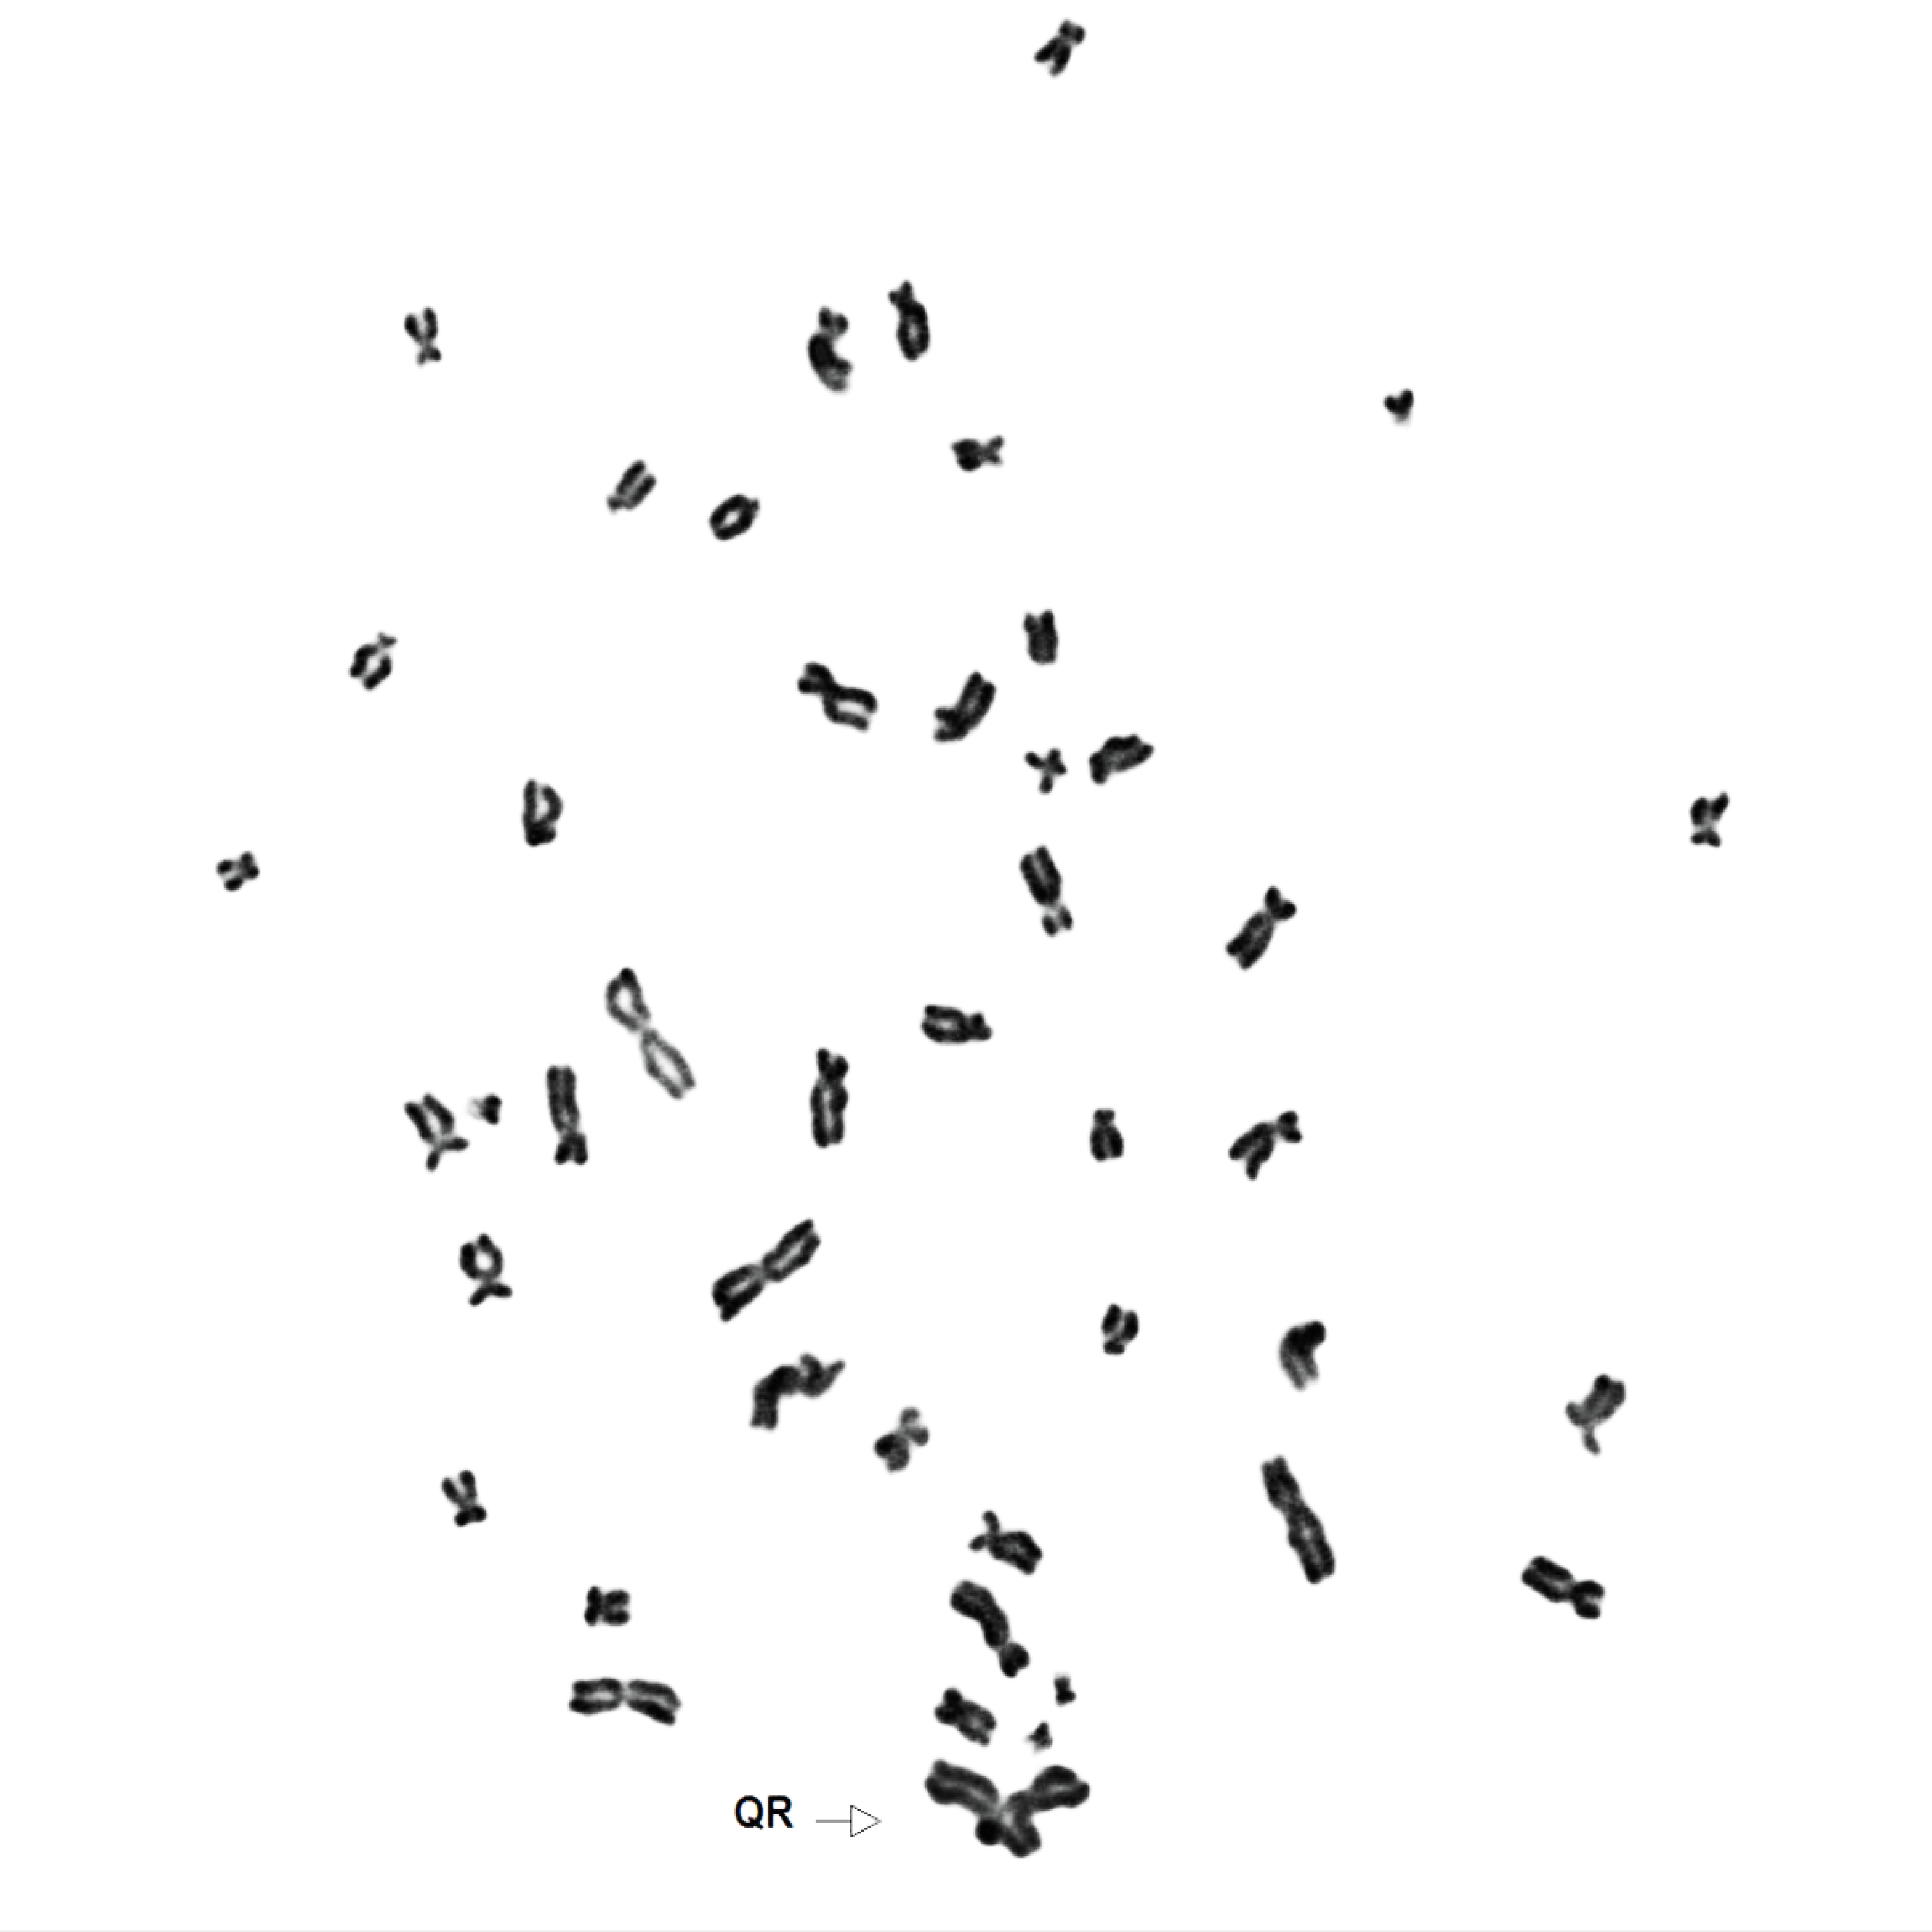

Das gefundene Gen codiert für ein Enzym, USP48, das einen wichtigen Regulationsfaktor für Proteine entfernen kann. Wenn USP48 in FA-Zellen nicht mehr vorhanden ist, reagieren die Zellen viel weniger empfindlich auf DNA-schädigende Substanzen und können die Schäden viel besser reparieren. „Unsere Ergebnisse zeigen, dass die Inaktivierung von USP48 die chromosomale Stabilität der FA-Zellen erhöht“ erklärt Joanna Loizou. „Das unterstreicht die Bedeutung dieses Enzyms in der Kontrolle der DNA-Reparatur und macht es zu einem vielversprechenden Ziel für Wirkstoffe. Wenn es gelänge, gezielt inhibierende Moleküle gegen USP48 zu entwickeln, wäre das ein völlig neuer potentieller Ansatz um die verheerenden Symptome von FA-Patienten zu mildern.“